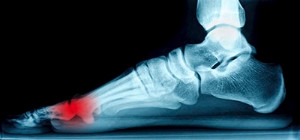

The tarsal tunnel is a canal that exists between the ligaments that spans across the foot and a portion of the bone. The nerves and tendons that are inside this tunnel allow mobility and enable the foot to easily point and flex. If a specific nerve called the tibial nerve inside this canal should become compressed, typically resulting from an injury, this condition is referred to as tarsal tunnel syndrome. Having flat feet is a possible reason for this condition, causing the tibial nerve to become strained. Certain health issues, such as arthritis and diabetes, may also cause the nerve to endure swelling and increased pressure. The nerve must be allowed to heal properly, and this may be accomplished by wearing a brace or supportive shoes. The discomfort that is experienced may be indicative of other foot-related conditions, so it’s advised to consult a podiatrist for a proper diagnosis

Tarsal tunnel syndrome, which can also be called tibial nerve dysfunction, is an uncommon condition of misfiring peripheral nerves in the foot. The tibial nerve is the peripheral nerve in the leg responsible for sensation and movement of the foot and calf muscles. In tarsal tunnel syndrome, the tibial nerve is damaged, causing problems with movement and feeling in the foot of the affected leg.

Tarsal tunnel syndrome is a condition in which there is a compression of the posterior tibial nerve. The posterior tibial nerve runs along the inside of the into the foot. Tarsal tunnel syndrome is named for the tarsal tunnel, which is a thin space along the inside of the beside the bones. This space contains various nerves, arteries, and tendons, and includes the posterior tibial nerve. The tibial nerve is the peripheral nerve in the leg responsible for sensation and movement of the foot and calf muscles. In tarsal tunnel syndrome the tibial nerve is compressed, causing tingling or burning, numbness, and pain.

Common causes of tarsal tunnel syndrome involve pressure or an injury. Injuries that produce inflammation and swelling in or around the tunnel may place pressure on the posterior tibial nerve. Direct pressure on the tibial nerve for an extended period of time, sometimes caused by other body structures close by or trauma to the tibial nerve, can result in tarsal tunnel syndrome. Diseases that damage nerves, such as diabetes or arthritis, may cause tarsal tunnel syndrome. Those with flat feet are at risk for developing the condition, as the extra pressure and strain placed on the foot may compress the posterior tibial nerve.